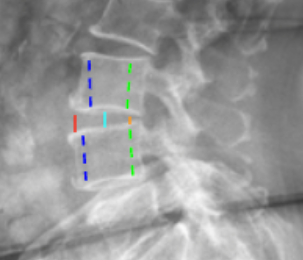

Disc Height Index (DHI)

Segmental Lordosis